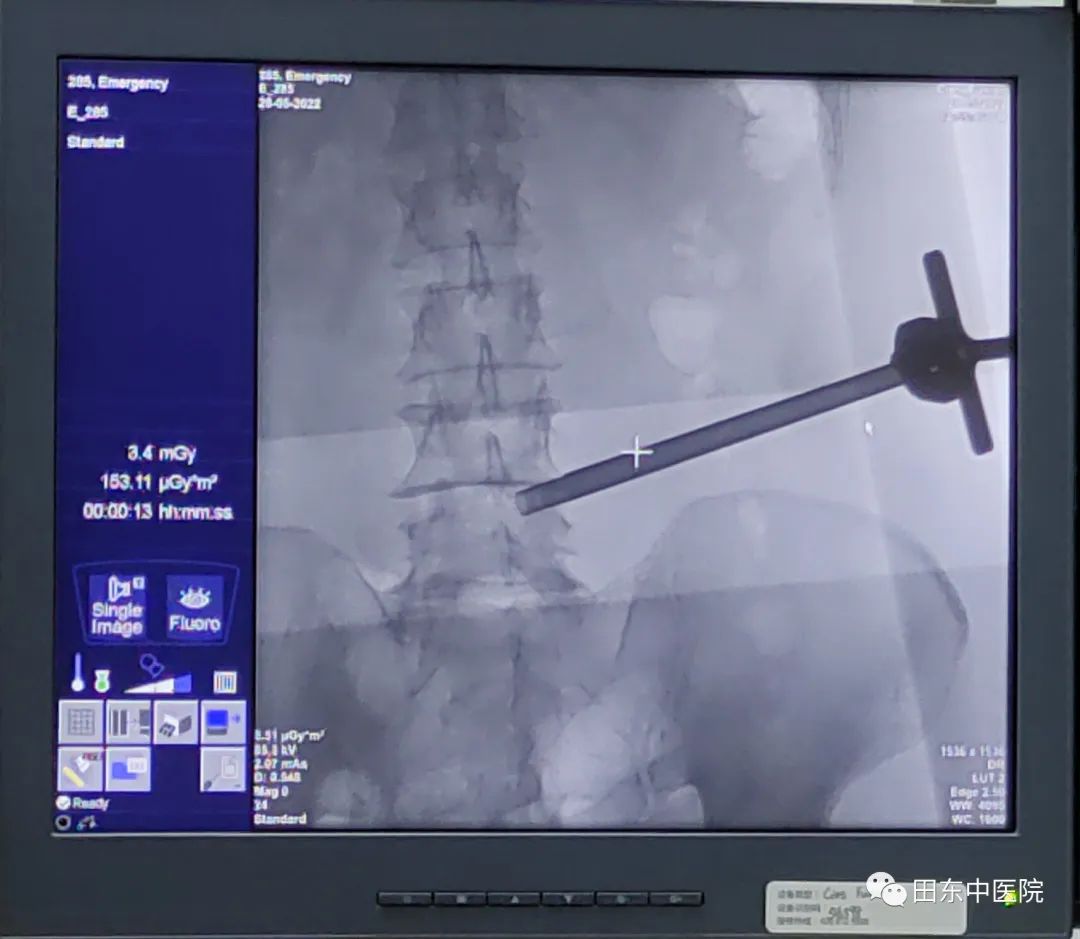

经过精心的术前准备,我院骨伤科二区医疗团队在覃奇文教授的指导下,由麻醉科医护人员协助,经过2个多小时的紧张手术,圆满完成首例椎间孔镜下腰椎间盘突出髓核摘除术,术后患者下肢麻痛症状消失。该技术在田东范围内属领先水平,填补了本地区相关技术领域空白。

▲以1厘米创口成功将突出椎间盘完整取出,术中出血量少,手术效果理想